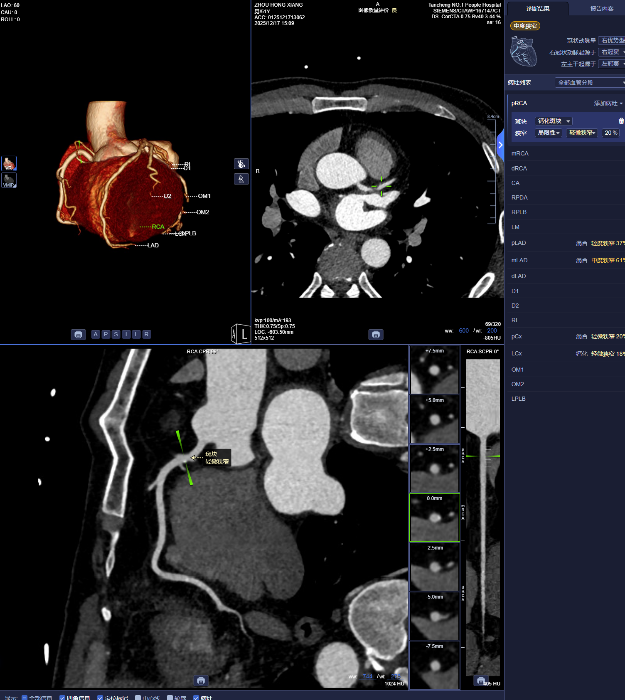

CPR图显示右冠中段钙化斑块,左前降支中段钙化斑块,左回旋支近端少许钙化斑块;无运动伪影。

VRT图可见冠脉主干及主要分支血管的走行及心腔的关系。